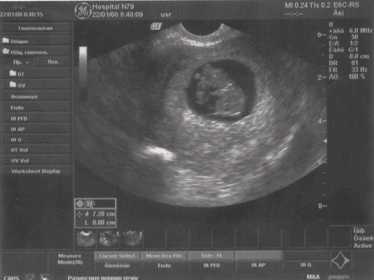

Толщина М-эхо, норма. 2Д.

УЗИ норамльной матки. 2Д.

УЗИ нормальной матки. 2Д.